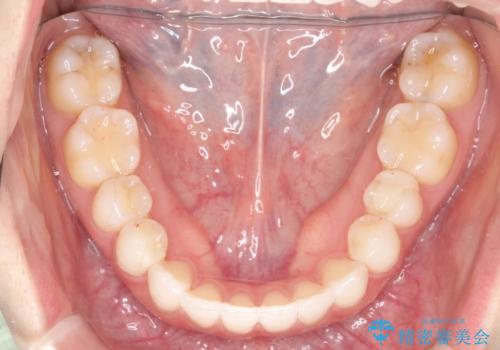

- 前歯の凸凹を主訴に来院されました。

インビザラインにて短期間で満足いく結果が得られたと大変喜ばれました。

歯と歯の間に僅かなスペースを作って配列していました。追加アライナーを1回行っています。